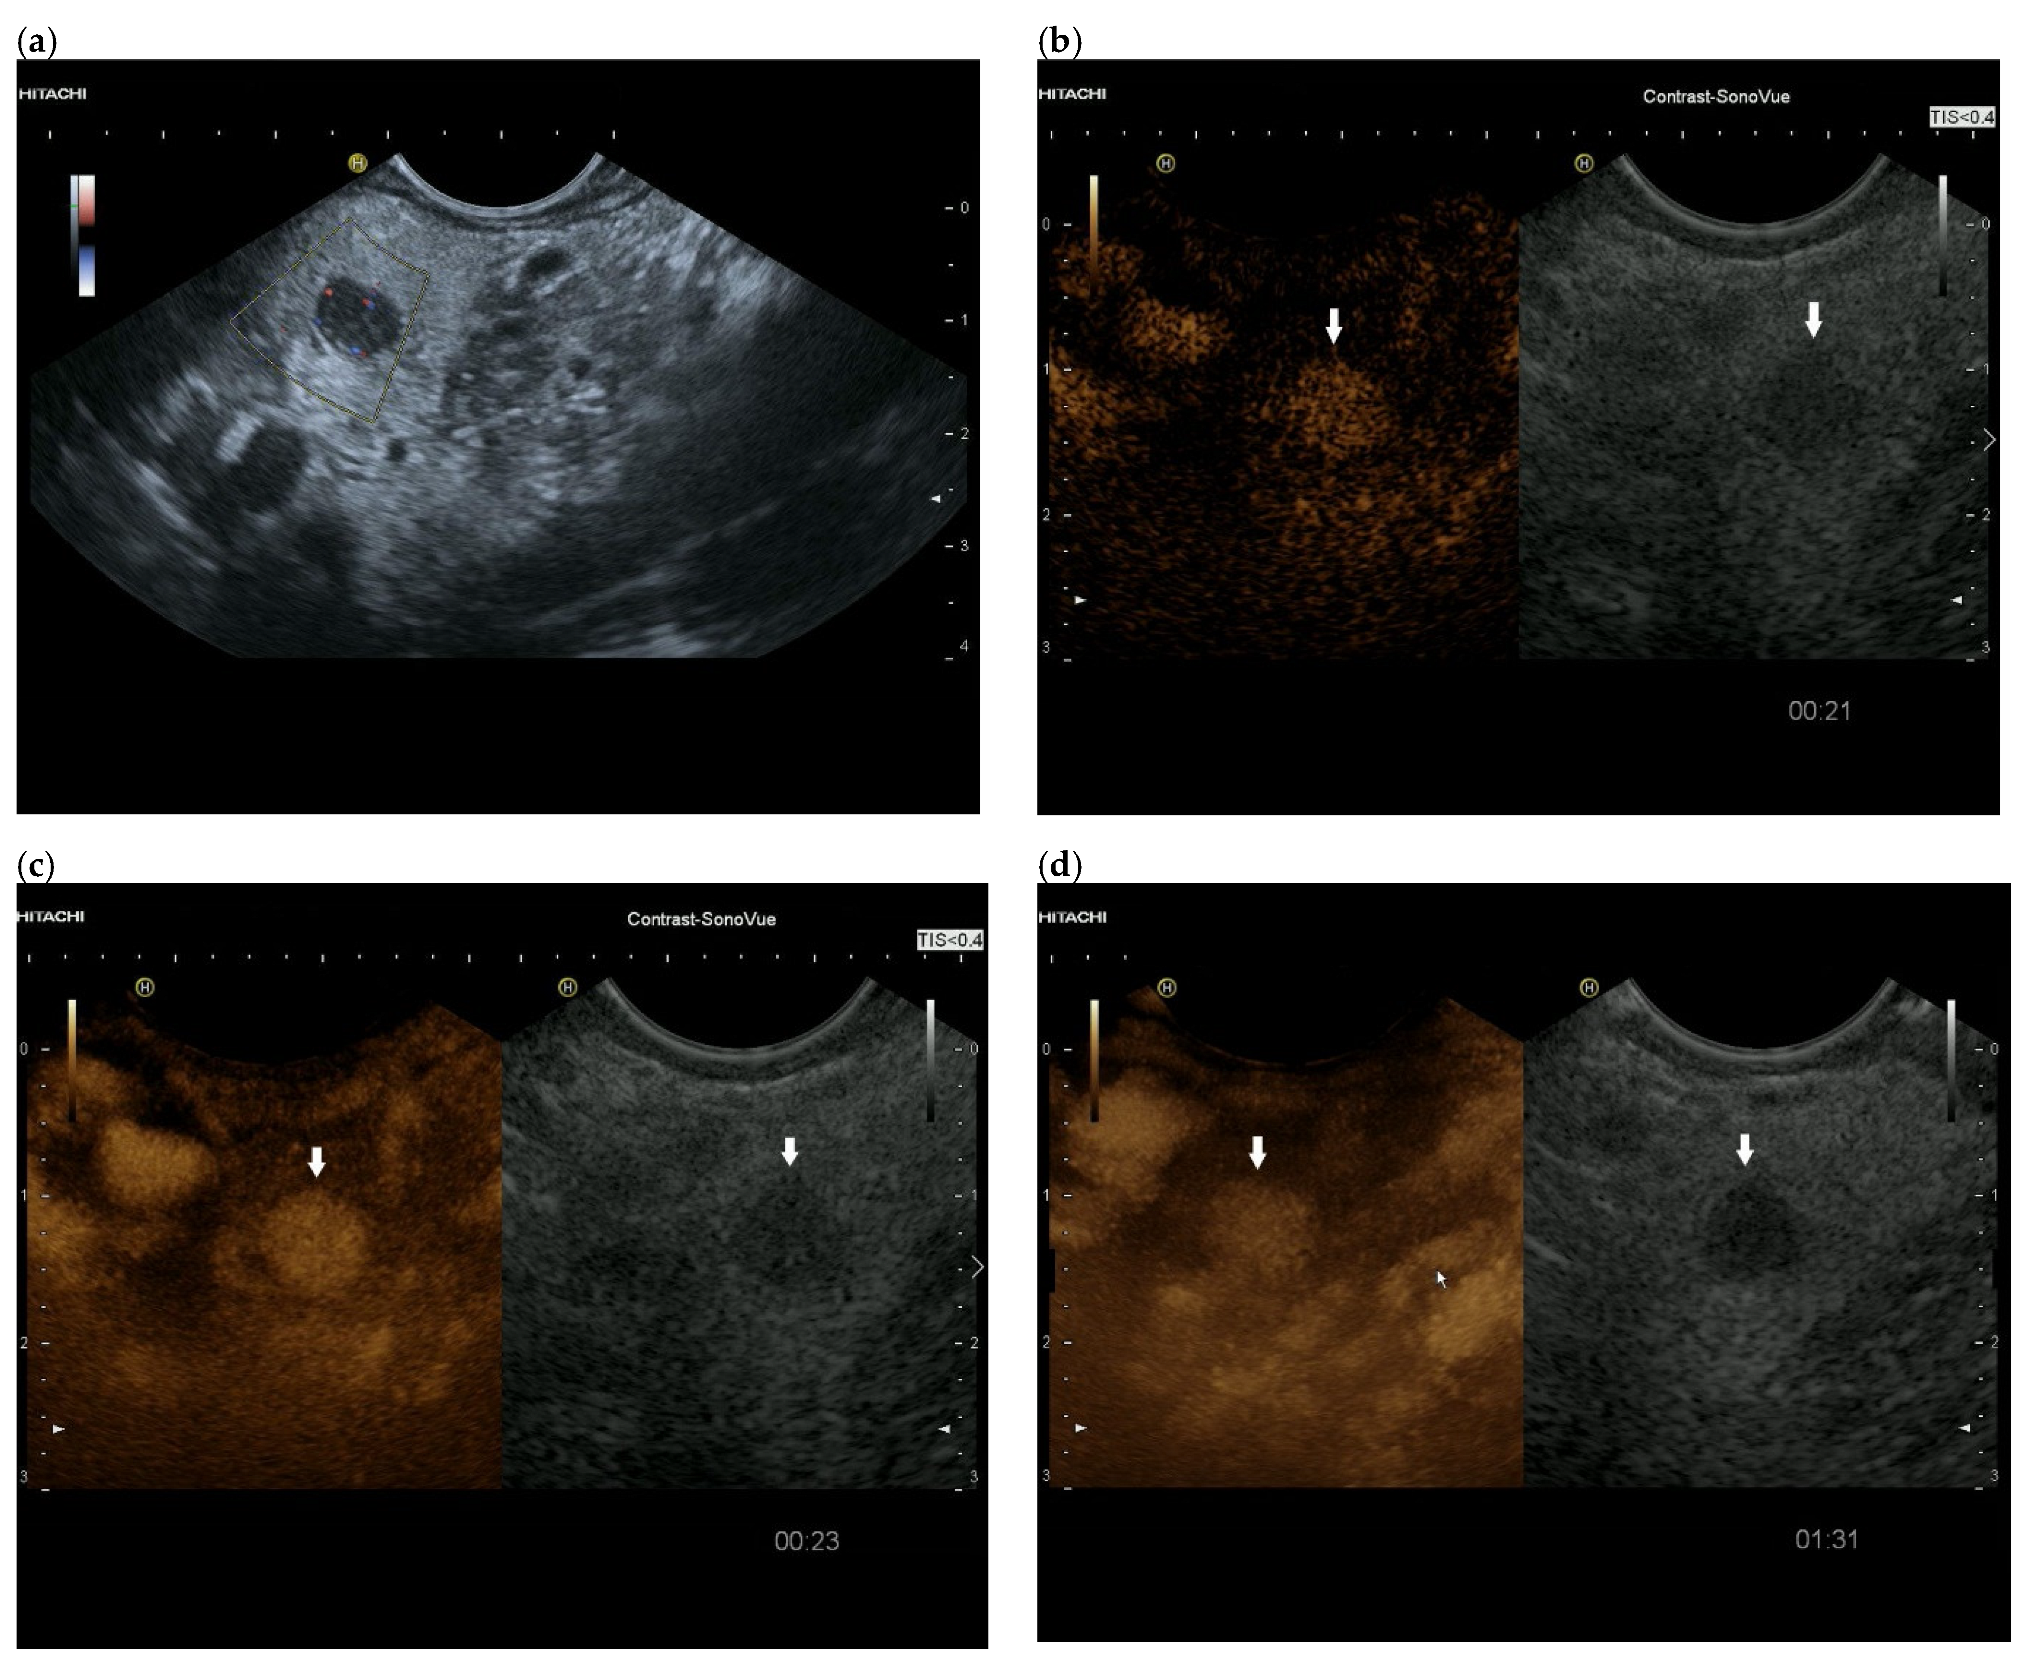

3.4. CEUS and CH-EUS

| Cases | CEUS | CH-EUS | ||

|---|---|---|---|---|

| Arterial Phase | Venous Phase | Arterial Phase | Venous Phase | |

| RCC metastases [83] (n = 4) | Hyperenhancement, Early | Hyperenhancement | ||

| RCC metastases [61] (n = 3) | Hyperenhancement, homogeneous pattern | Slow washout | ||

| RCC metastasis [86] (n = 1) | Hyperenhancement, Inhomogeneous pattern | No washout | ||

| Melanoma metastasis [63] (n = 1) | Iso- to slightly hypoenhanced | Hypoenhanced | ||

| Melanoma metastasis [87] (n = 1) | Isoenhanced | Hypoenhancement of the peripheral rim, central non-enhancement | ||

| Melanoma metastasis [61] (n = 1) | Isoenhanced, heterogeneous | Fast washout | ||

| SCLC metastasis [83] (n = 1) | Hyperenhancement | Rapid washout | ||

| Breast, ovarian, colon metastases, sarcoma metastases [61] (n = 6) | Hypoenhancement, homogeneous or heterogeneous | Fast or slow washout | ||

| Lymphoma metastasis [61] (n = 1) | Hyperenhancement, homogeneous pattern | Fast washout |